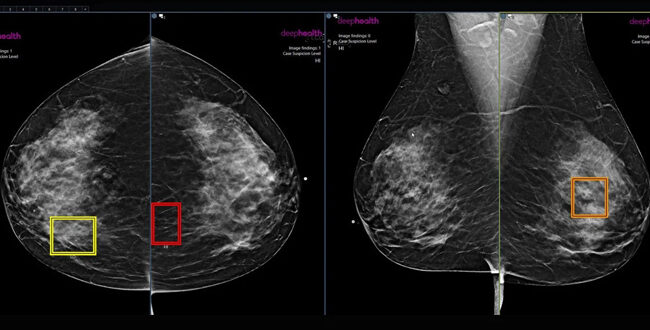

স্তন ক্যান্সার শনাক্তে কৃত্রিম বুদ্ধিমত্তা (এআই) কার্যকর ভূমিকা রাখতে পারে বলে একটি মার্কিন গবেষণায় উঠে এসেছে। স্তন-স্ক্রিনিং প্রোগ্রাম ম্যামোগ্রাফি স্ক্রিনিংয়ে কৃত্রিম বুদ্ধিমত্তা (এআই) ব্যবহারে দারুণ ফল পেয়েছেন গবেষকরা। তাদের দাবি, এআই দিয়ে স্ক্যান করা হলে স্তন ক্যান্সার শনাক্ত হওয়ার সম্ভাবনা ২১ শতাংশ বেশি।

রেডিওলজিক্যাল সোসাইটি অব নর্থ আমেরিকার (আরএসএনএ) বার্ষিক সভায় এই ফল উপস্থাপন করে রেডিওলজি জায়ান্ট র‌্যাডনেটের মালিকানাধীন এআই ফার্ম ডিপহেলথ।

১২ মাসে সাত লাখ ৪৭ হাজার ৬০৪ জন নারীর ওপর ম্যামোগ্রাফি স্ক্রিনিংয়ের পর এই ফলাফল উপস্থাপন করে র‌্যাডনেট।

অনুষ্ঠানে জানানো হয়, গবেষণার আওতাধীন নারীদের অনেকে ম্যামোগ্রাফিতে মার্কিন খাদ্য ও ওষুধ প্রশাসনের এআই সফটওয়্যার বেছে নেন। চিকিৎসকের চোখ এড়িয়ে গেলেও ওই সফটওয়্যার ক্যান্সারের জীবাণু শনাক্তে সহযোগিতা করায় ম্যামোগ্রাফিতে এটি ‘দ্বিতীয় চোখ’ হিসেবে বিবেচনা করা হয়।

এই প্রকল্পে যেসব নারী অংশগ্রহণ করেন বাকিদের চেয়ে তাদের মধ্যে ক্যান্সার শনাক্তের হার ৪৩ শতাংশ বেশি ছিল বলে জানানো হয়।

তবে স্তন ক্যান্সারের উচ্চ ঝুঁকিতে থাকা নারীদের ওপরই শুধু এআইয়ের পরীক্ষা চালানো হয়। ফলে ৪৩ শতাংশ বেশি শনাক্ত হারকে বিবেচনায় নেয়া হয়নি। পরে সার্বিকভাবে এই হার ২২ শতাংশ বলে জানানো হয় এবং শেষ পর্যন্ত তা ২১ শতাংশের কম নয় বলে যুক্তি উপস্থাপন করা হয়।